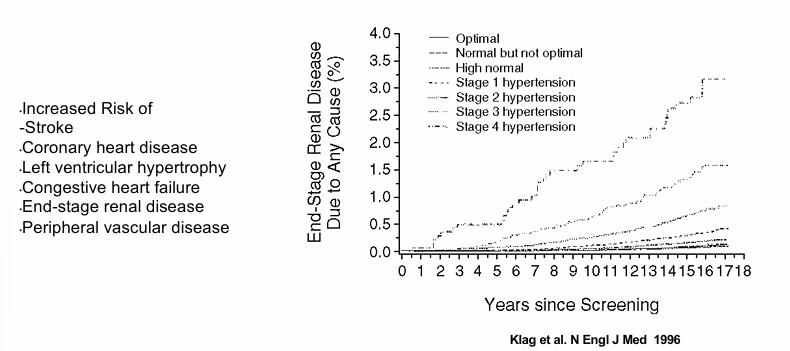

suboptimal blood pressure control among US adults with hypertension